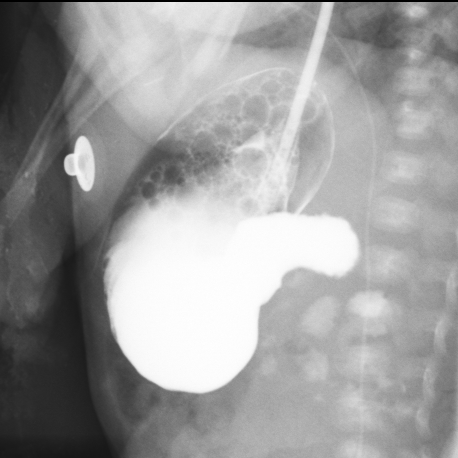

造影提示十二指肠梗阻

造影提示十二指肠梗阻 术中见梗阻部位为十二指肠降部,梗阻原因为环状胰腺